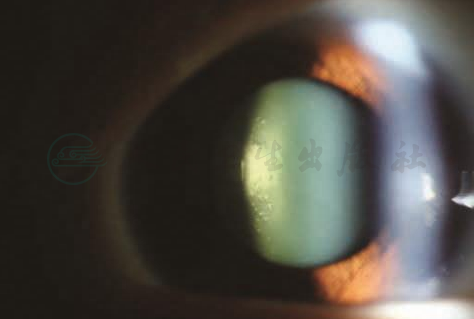

就各种类型白内障的发病率来说,BDES、BMES、VIP等大型的流行病学调查研究发现糖尿病与后囊下型白内障(图1)、皮质型白内障和核性白内障的发病相关。

图1糖尿病性白内障

患者女,29岁,1型糖尿病,双眼视力下降2年,出现后囊下型白内障